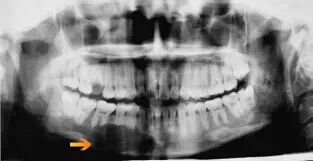

体格检查发现:右侧下颌骨可扪及一 2*4cm 大小肿块,质硬,不可活动,与周围组织分界欠清。表面皮肤无红肿溃烂。左侧腮腺区可见腮腺手术术后瘢痕。未扪及肿大淋巴结。全景片示:右侧下颌第一前磨牙至下颌右侧第一磨牙骨质边界不清的边界,累及牙齿呈浮动的牙齿外观,有牙根吸收。